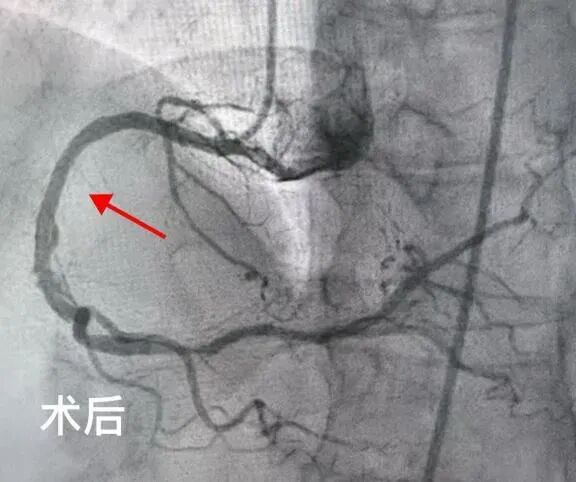

2025年5月,吉林市人民医院心内五病区收治了一位70岁的老年女性患者。该患者反复心绞痛1年,近3天症状加重。入院后,冠脉造影检查明确显示其存在严重的三支血管病变。通常情况下,冠脉搭桥手术是此类患者的首选治疗方案,但家属综合考虑患者年龄和身体状况,最终选择冠脉介入治疗。经心内五病区张金子主任团队审慎评估,决定分两次为患者实施支架植入术。

第一次手术顺利完成,在患者右冠状动脉植入两枚支架,心绞痛症状有所缓解,但仍反复发作。经过两周的精心调整,5月25日,患者再次入院接受第二次支架植入手术。然而,术后返回病区时,患者突发严重并发症——因剧烈恶心呕吐,吐出大量鲜血。由于患者既往有慢性胃炎病史,这一突发状况导致其病情急剧恶化,生命危在旦夕。 专 家 介 绍 吉林市人民医院心血管内科五病区主任 熟练处理各种疑难复杂病变,急性心梗介入治疗,慢性闭塞病变(CTO),左主干病变,分叉病变,血栓病变,口部病变,迂曲钙化病变,桥血管病变等介入治疗,熟练掌握各种分叉支架术式(crush,cullote),IABP(主动脉球囊反搏泵)辅助下高危病人介入治疗,IVUS(血管内超声),OCT(光学相关断层扫描技术)及FFR(冠脉血流储备检查)等各种设备及腔内影像学检查,为一名成熟独立术者。 以第一申请人申请市级课题一项;共发表论文11篇,其中核心期刊4篇;参与“国家级自然基金”课题1项;2018年于北部战区总医院心内科完成冠脉介入基地学员培训并获得冠脉介入资质证书;2020年于北部战区总医院心内科完成心血管专科医师培训,同年取得中国医师协会颁发的专科医师规范化培训合格证书。2022年于北部战区总医院心内科完成培训并获得结构性心脏介入资质证书。 吉林市昌邑区人大代表;吉林省老年心血管预防康复委员;吉林省中西医结合学会第一届心衰防治与康复专业委员会委员;2022年昌邑区十九届人民代表大会代表;2022年度吉林市昌邑区优秀人大代表;2022年吉林市统战最美统战人新阶层创新之星;2023年度吉林市昌邑区优秀人大代表。